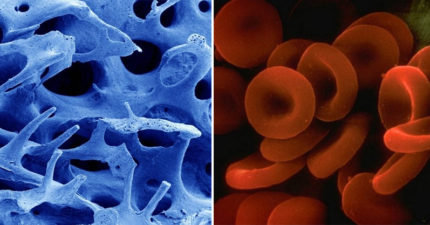

人體器官「顯微鏡下的模樣」 女生排卵像火山爆發